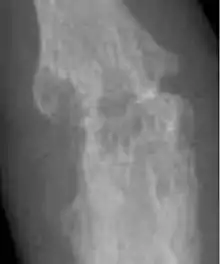

| A hand affected by rheumatoid arthritis, an autoimmune form of arthritis | |